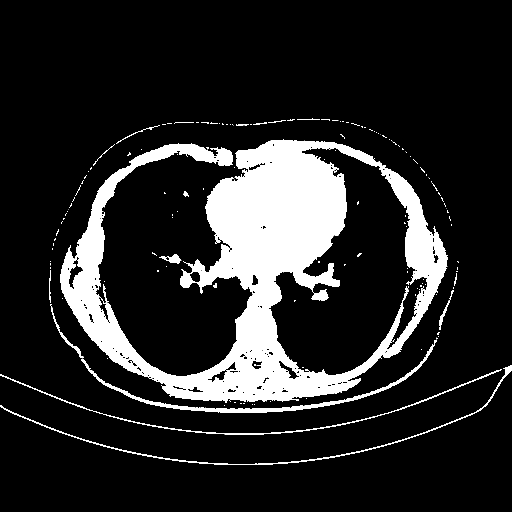

Original VENOUS CT scan

Full window (WL 1023.5, WW 4095 β†’ Low βˆ’1024, High +3071)

Actual HU range: [-1024.0, 3071.0]